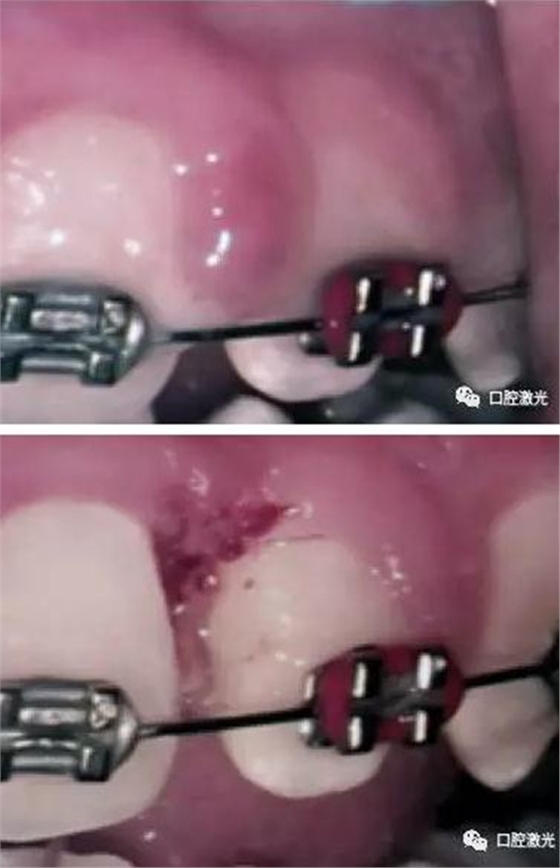

由于藥物或正畸引起的牙齦增生組織去除

表麻下牙齦增生的激光切除即可效果